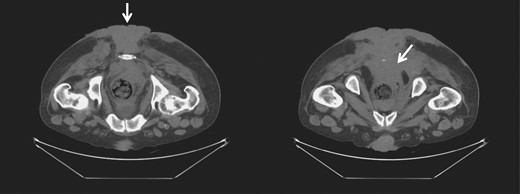

Four months later, after completion of the chemoradiotherapy, there was a significant resolution of the tumor (Fig. 3). No lesions could be felt on the rectal exam. The endoscopy and CT scan after another three months confirmed regression without presence of lesions. The scarred and necrotic soft tissue appeared to be residual from the chemoradiation and was debrided.

Gross image (A) and CT of the pelvis and perineum (B) showing tumor resolution and residual lesions after chemoradiation therapy.